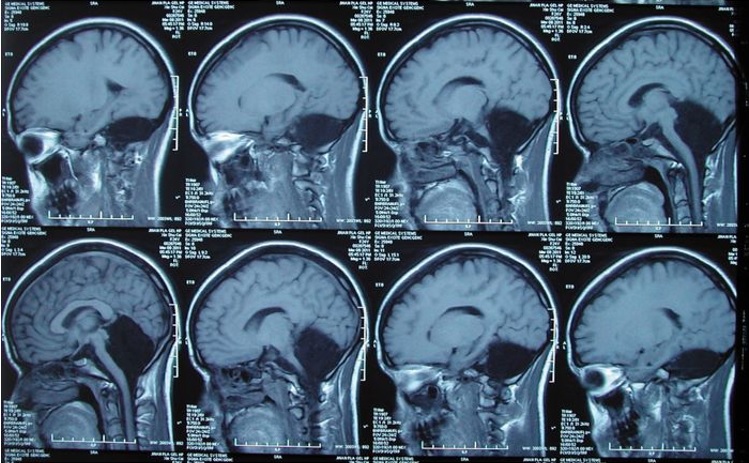

Егер сізге миыңыздың ең негізгі әрі маңызды бөлігінсіз өмір сүріп келгеніңізді айтса, қандай күйге түсер едіңіз? Қытай қызы ширек ғасырға жуық, яғни, 24 жыл бойы осындай кемістікпен өмір сүріп келгенін білмеген. Оның осынша уақыт бойы қалай өмір сүріп келгеніне дәрігерлер таң-тамаша қалып отыр. 24 жастағы қытай қызының мишығының жоғын анықтаған тәжірибелі дәрігерлер мұндай жағдай медицина тарихында өте сирек кездесетінін алға тартып отыр. Біз сөз етіп отырған қытай қызы дәрігерлерге жүрегі айнитынын әрі лоқситынын айтып, шағымданып келеді. Тексере келгенде пациенттің мишығы жоғы анықталған. Былайша «кіші ми» деп аталатын мишық қимыл-қозғалысты үйлестіреді, яғни, тепе-теңдіктің сақталуын қамтамасыз етеді, бұлшық еттің қызметін реттейді. Сол себепті, ол адам ағзасының ең маңызды бөлігі болып табылады. Мишық мидың артқы қабатында, яғни, адамның желке тұсында орналасқан. Мишық мидың қабымен байланысқанымен оның қызметін адам санасы бақылай алмайды. Пациент тек төрт жасында ғана жүрген және жиырма жыл бойы аяғын нық басып жүре алмаған, өйткені, мишық жауапты болып табылатын тепе-теңдікті сақтауы қиынға соққан. Десе де, бойжеткеннің ағзасы осынау кемістікке де «бой үйреткен», яғни, өзінше бейімделген. Қимыл-қозғалысындағы тепе-теңдікке аса мән бермей келгені анықталды.

Brain журналында жарық көрген дәрігерлердің (қытай қызын қараған) есебіне қарағанда, бойжеткеннің бойынан тіпті мишықтың титтей де бір жасушасы табылмаған. Зерттеуден белгілі болғандай, пациенттің балалық шағында өзінің осынау кемістігіне барынша бейімделген. Мидың бұл қызметін өзге бөлігі «атқарып» келген. Алайда, бұл өз кезегінде қыздың сөйлеу қабілетіне нұқсан келтіріпті. Мұндай жағдай медицина тарихында сегіз рет болған екен. Мұндай кемістік шараналардың бойынан анықталған әрі олардың көбісі шетінеп кеткен.